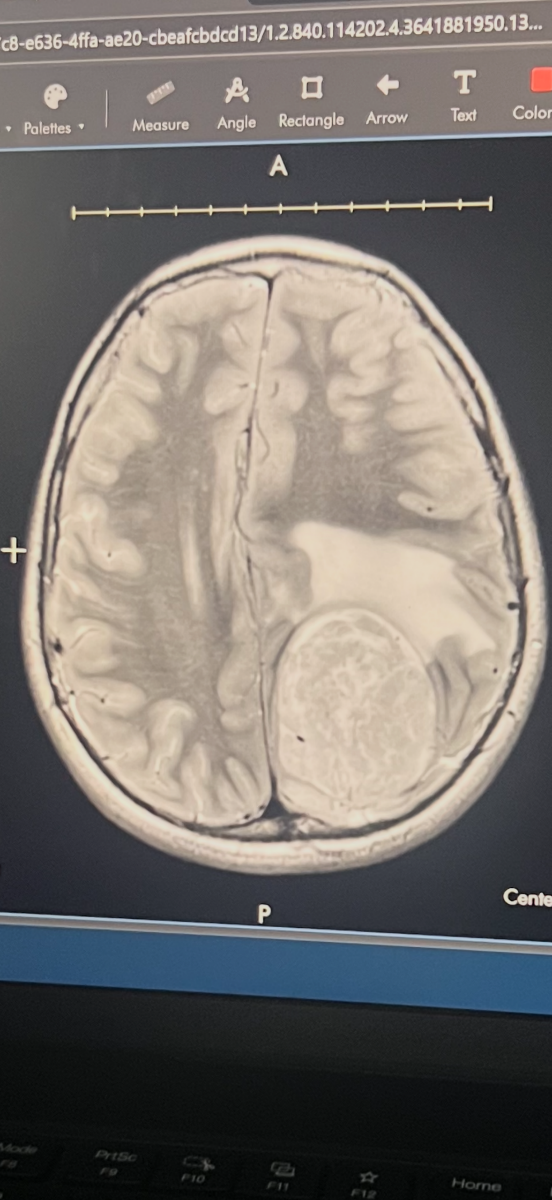

On February 18, 2026, Derek (affectionately known as Baby D) was sent to Helen DeVos Children’s Hospital for an MRI after his eye doctor noticed swelling and traces of blood on his optic nerves. After several tests and blood work, Derek’s MRI revealed a massive brain tumor measuring 5.72 cm that needed to be removed immediately. He was admitted to the PICU, and his world—and his family’s—changed overnight. Derek underwent brain surgery on February 20, 2026, and spent nearly a week in the hospital.

On March 11, Derek’s family received the pathology results: the tumor was a high-grade Anaplastic Meningioma, a rare and aggressive form of cancer. In just two weeks, Derek will face another brain surgery to remove the remaining portion of the tumor, followed by radiation treatments. These treatments will take this fun-loving, adventurous 10-year-old away from baseball, school, and the summer he was so excited for. But if you know Derek, you know he is strong, brave, and full of hope. He’s staying positive and believes the tumor won’t come back after treatment. With very little research available on this rare grade of meningioma, Derek’s family is taking everything one day at a time.